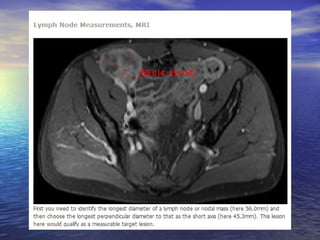

Avaliação dos linfonodos:

Linfonodos: eixo curto ≥ 15mm: lesão mensurável (target lesion);

Linfonodos: eixo curto < 10mm: “não patológicos”;

Linfonodos: eixo curto ≥ 10mm e < 15mm: nontarget lesions;